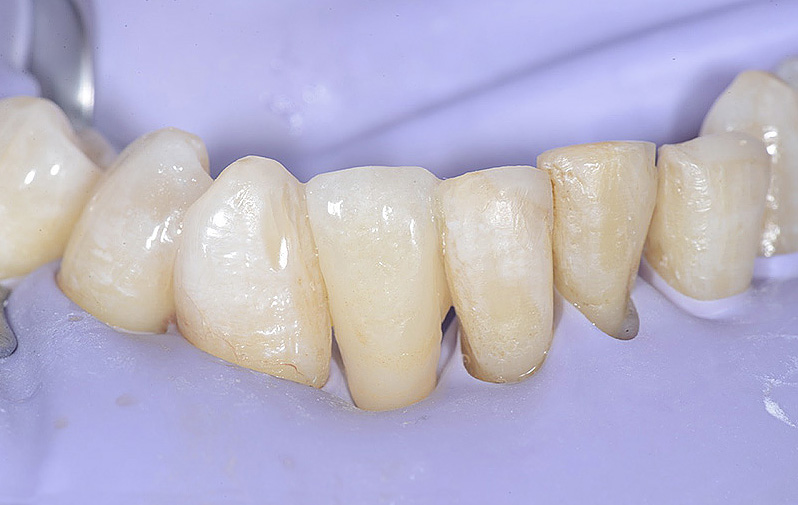

Vengono utilizzati 2 tipi di provvisori: il primo, cementato ai denti vicini, viene utilizzato dal momento dell’estrazione del dente fino ad impianto osteointegrato (circa 6 mesi); il secondo, avvitato direttamente all’impianto, ha una funzione di prova estetica ma soprattutto di guida per la maturazione dei tessuti gengivali peri-implantari portandoli verso la maturazione completa prima di posizionare la corona finale in disilicato di litio.